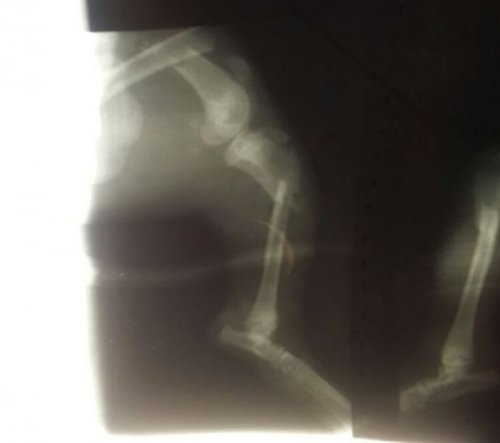

Ветеринары предложили усыпить доставленного пса, однако фонд настоял на спасении животного и проведении необходимой операции. Как оказалось, у него были переломаны задние лапы в семи местах, а также сломан крестец. Операция длилась в течение 8 часов, выставленный ветклиникой счёт составил 15.000 рублей. Операцию делали в долг, пока деньги на её оплату поступали на счёт фонда от неравнодушных Интернет-пользователей.